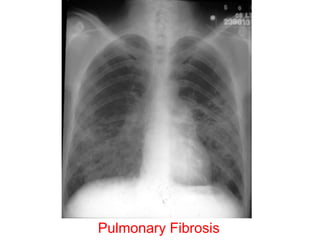

Pulmonary Fibrosis